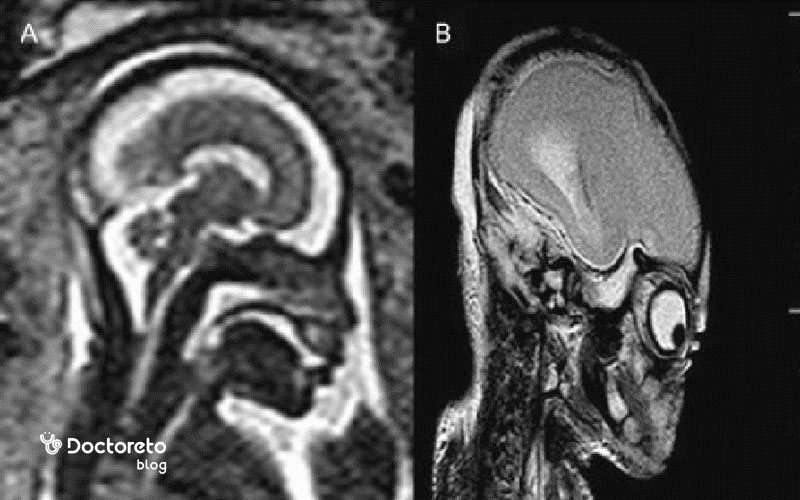

حتی در صورت تشخیص کوچکی سر جنین در سونوگرافی، پزشک بعد از تولد بررسیهای مورد نیاز را انجام میدهد تا بتواند به صورت دقیقتر، میکروسفالی بودن نوزاد را تشخیص دهد. MRI و آزمایش ژنتیک میتوانند میزان تشخیص میکروسفالی را بهبود ببخشند و بنابراین به عنوان بخشی از بررسیهای اولیه تشخیصی، توصیه میشوند.

میکروسفالی را میتوان در رحم با استفاده از اسکن اولتراسوند تشخیص داد، تکنیکی که امواج صوتی با فرکانس بالا و فناوری رایانه را برای تولید تصاویر تشخیصی از رگهای خونی، اندامها و بافتهای در حال رشد نوزاد ترکیب میکند. با این حال، میکروسفالی معمولاً با این تکنیک تا سه ماهه سوم قابل مشاهده نیست و برای تشخیص میکروسفالی در سونوگرافی، حداقل باید تا اواخر سه ماهه دوم بارداری صبر کرد. پزشک معمولاً در تصاویر اولتراسوند به دنبال شواهدی از سر غیرطبیعی کوچک میگردد. حتی در صورتی که مشاهدات پزشک در تصاویر سونوگرافی، کوچک بودن سر نوزاد را نشان دهد، هنوز هم نمیتوان تا زمان تولد و انجام معاینات دقیق فیزیکی، میکروسفالی بودن جنین را تشخیص داد.